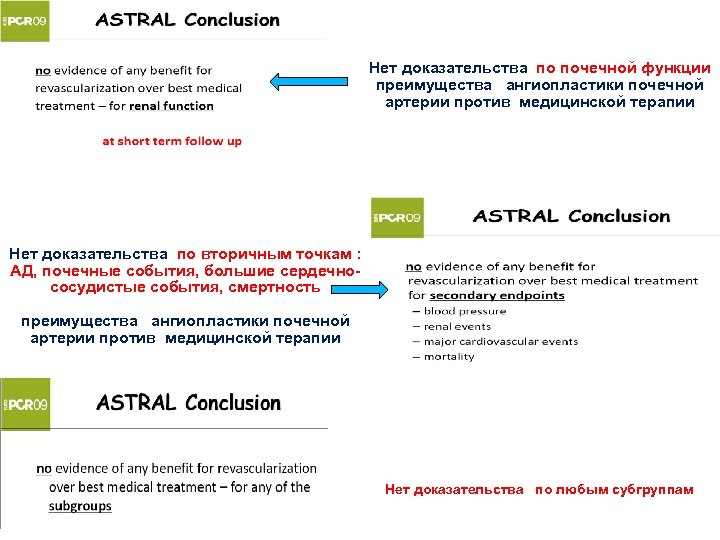

Нет доказательства по почечной функции преимущества ангиопластики почечной артерии против медицинской терапии Нет доказательства по вторичным точкам : АД, почечные события, большие сердечнососудистые события, смертность преимущества ангиопластики почечной артерии против медицинской терапии Нет доказательства по любым субгруппам

Нет доказательства по почечной функции преимущества ангиопластики почечной артерии против медицинской терапии Нет доказательства по вторичным точкам : АД, почечные события, большие сердечнососудистые события, смертность преимущества ангиопластики почечной артерии против медицинской терапии Нет доказательства по любым субгруппам